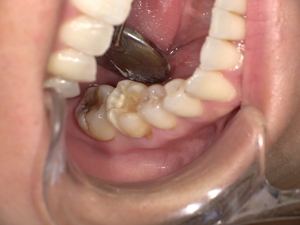

治療前の状態:古い被せ物が健康と審美性を損なう

診察の結果、下奥歯に装着されていた金属の被せ物は歯にしっかり適合しておらず、隙間から 虫歯が再発 していました。さらに別の歯の詰め物も劣化しており、口腔内全体でリスクが高い状態です。

Before

- 古い被せ物は色と形が不自然

- 歯茎との境目に虫歯が再発